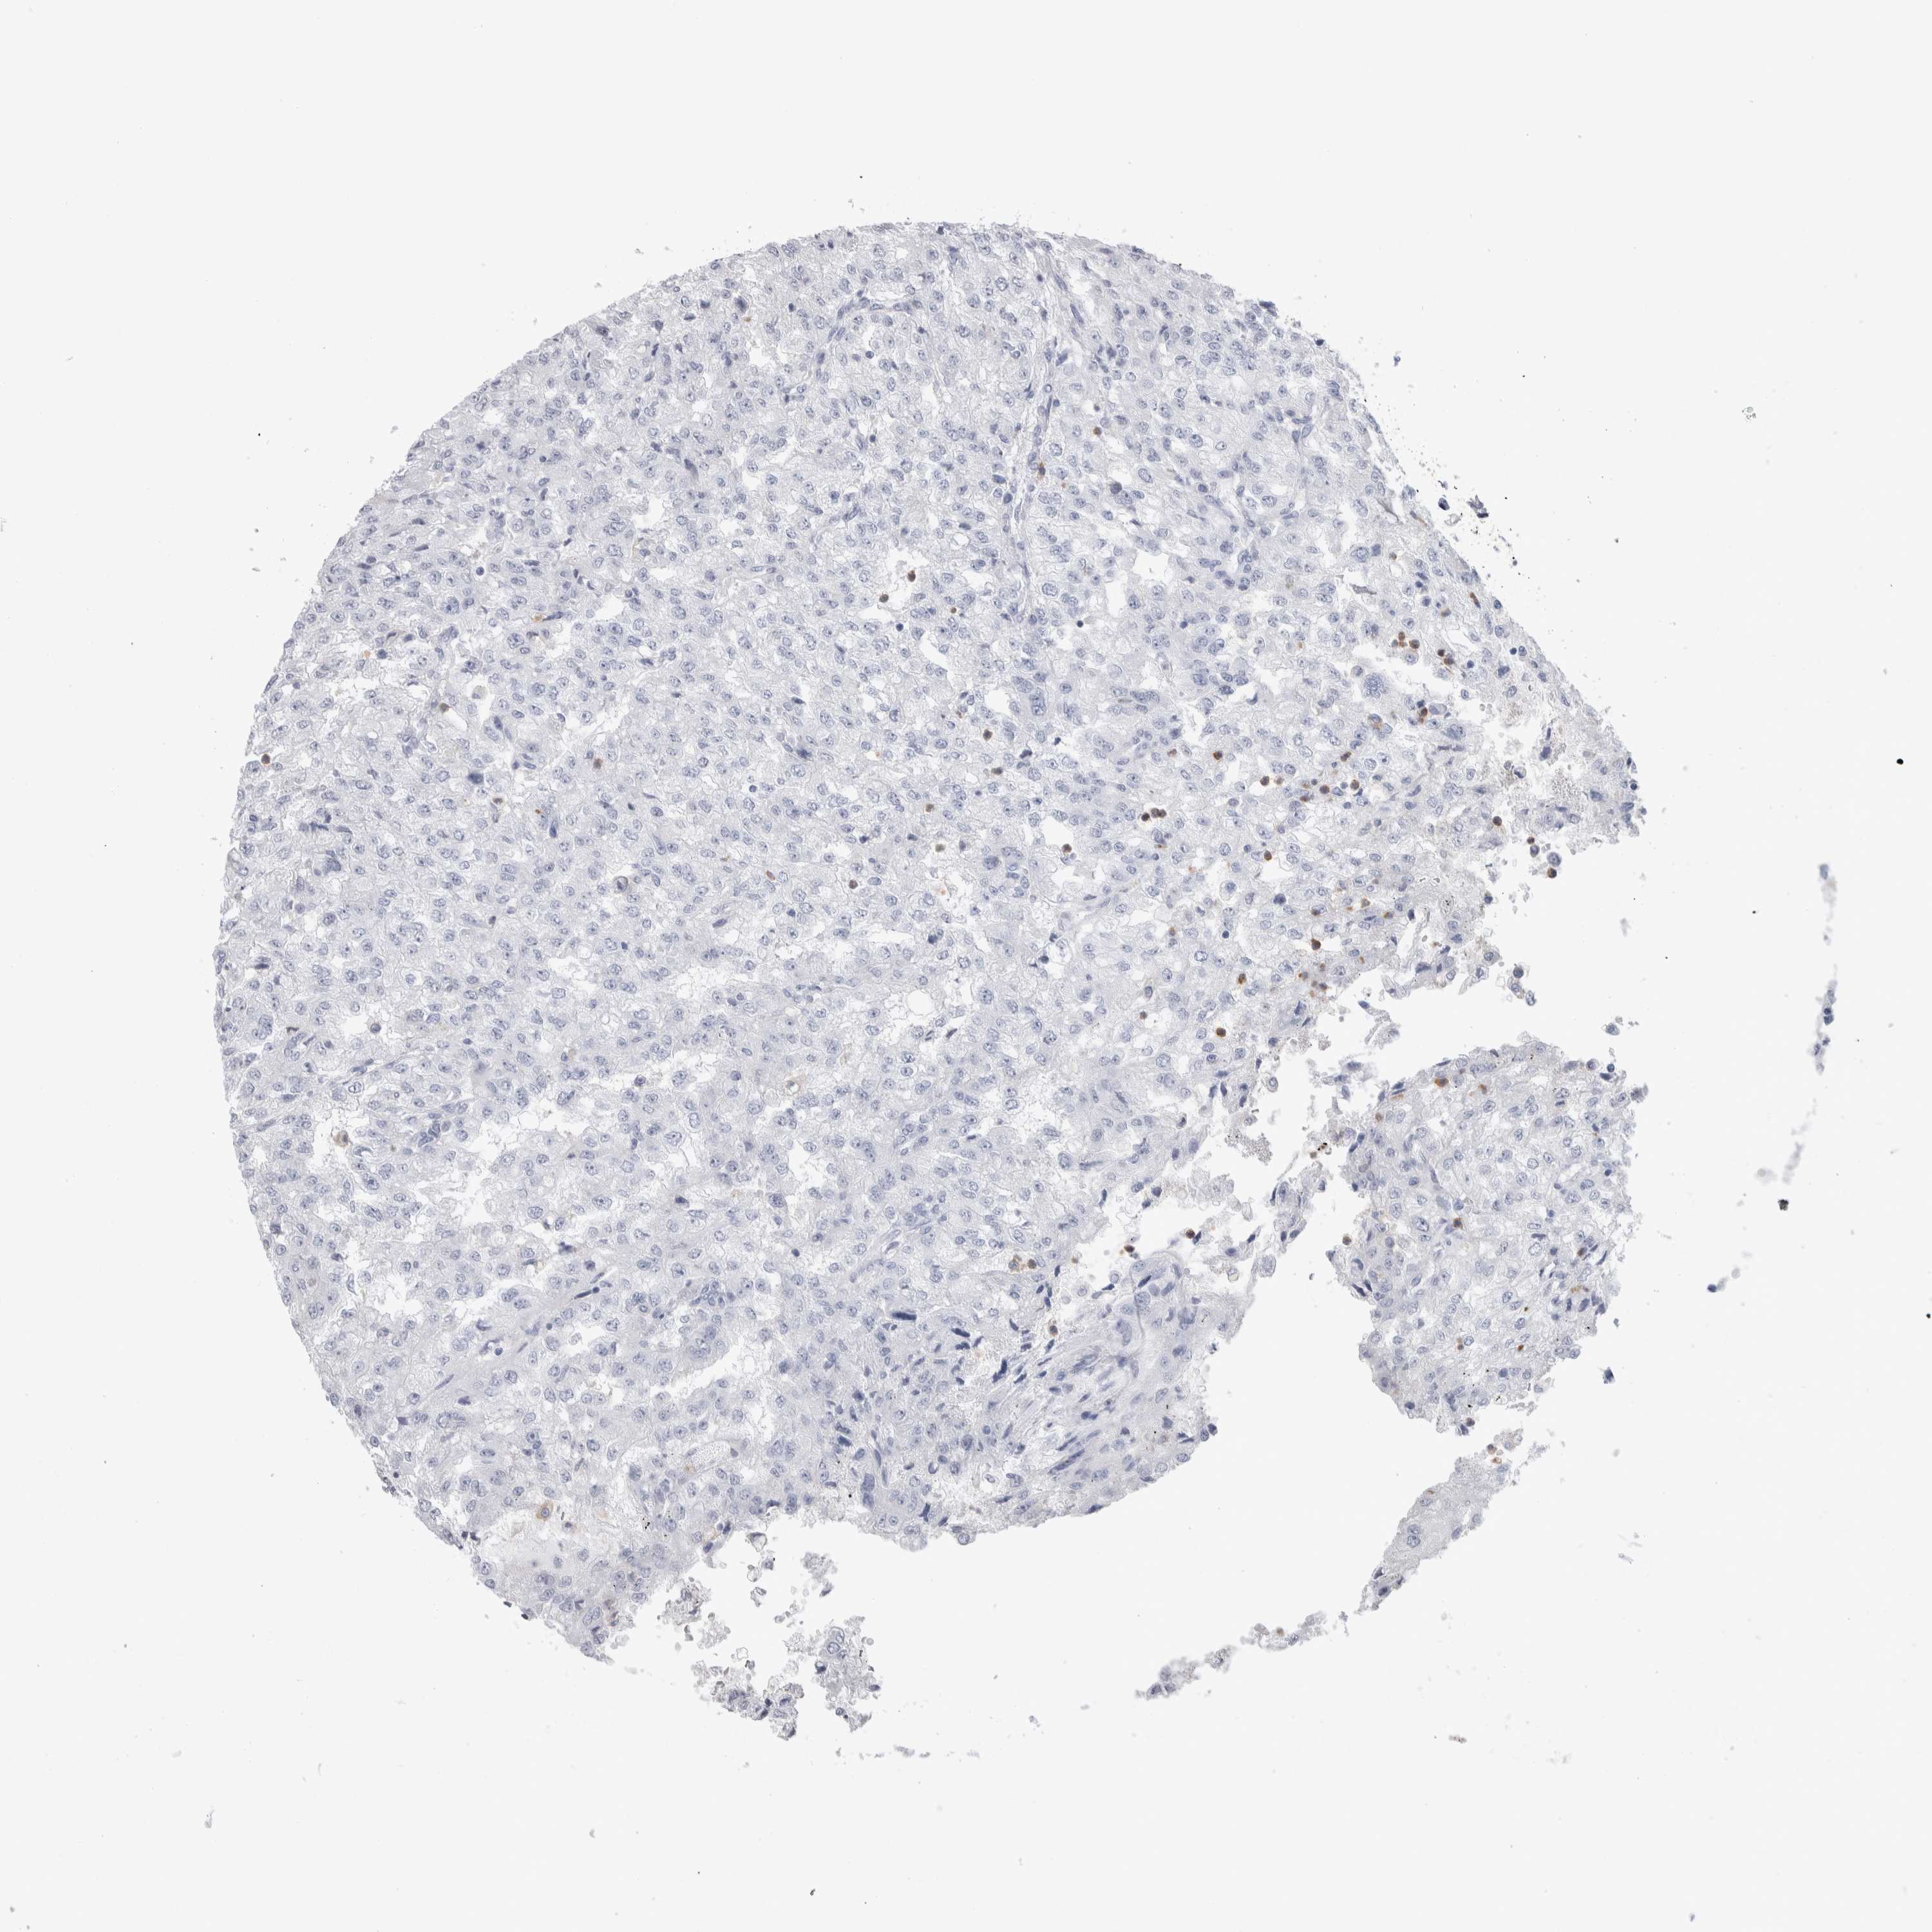

KIDNEY RENAL CLEAR CELL CARCINOMA (VALIDATION) - Interactive survival scatter ploti

LURAP1L is validated prognostic, high expression is favorable in Kidney Renal Clear Cell Carcinoma (validation)

: 4.03

Average pTPM 8.9

Number of samples 100